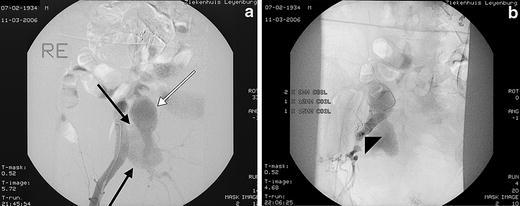

Ruptured aneurysms of the internal iliac artery (IIA) are rare and challenging to treat surgically. Due to their anatomic location they are difficult to operate on and perioperative morbidity is high. An endovascular approach can be helpful. We recently treated a patient with a ruptured IIA aneurysm in the interventional radiology suite with embolization of the side-branch of the IIA and placement of a covered stent in the ipsilateral common and external iliac arteries. A suitable stent-graft was not available initially and had to be brought in from elsewhere. An angioplasty balloon was temporarily placed across the ostium of the IIA to obtain hemostasis. Two hours later, the procedure was finished by placing the stent-graft.